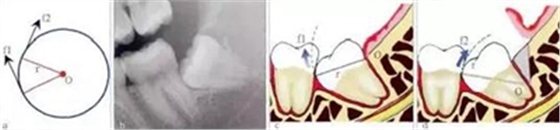

3.3.1 轉(zhuǎn)動(dòng)軸心與圓弧運(yùn)動(dòng)

這一原理在前傾或水平阻生智齒的拔除中運(yùn)用最廣??梢酝ㄟ^改變牙體轉(zhuǎn)動(dòng)脫位時(shí)的運(yùn)動(dòng)軸心,來改變牙體上各點(diǎn)的運(yùn)動(dòng)方向(圖4),從而避開阻力而使牙齒脫位。但在此過程中,牙槽窩的擠壓變形仍不可避免。尤其是舌側(cè)骨板的骨折,更是經(jīng)常發(fā)

生的事件。要進(jìn)一步減少對(duì)牙槽窩的擠壓,則需要對(duì)牙根進(jìn)行進(jìn)一步的切割。

圖4 轉(zhuǎn)動(dòng)軸心與圓弧運(yùn)動(dòng)。在圓周運(yùn)動(dòng)(旋轉(zhuǎn))中,圓周上所有點(diǎn)的運(yùn)動(dòng)方向(f1、f2)均為切線方向,與通過該點(diǎn)的半徑(r)相垂直(圖a)。當(dāng)牙齒發(fā)生旋轉(zhuǎn)脫位時(shí),其阻力點(diǎn)的運(yùn)動(dòng)方向會(huì)隨著轉(zhuǎn)動(dòng)的軸心點(diǎn)的變化而變化,從而避開阻力。前傾

阻生智齒(圖b)脫位時(shí),阻力分析如圖c所示,因阻力點(diǎn)位于旋轉(zhuǎn)中心(O)的下方,旋轉(zhuǎn)脫位時(shí),其阻力點(diǎn)的運(yùn)動(dòng)方向(f1)是向前上的,被鄰牙所阻擋。如果按照?qǐng)Dd所示,去除遠(yuǎn)中骨質(zhì)(灰色部分)或切割牙體(r)后,旋轉(zhuǎn)中心(O)下移,阻

力點(diǎn)的運(yùn)動(dòng)方向就改變?yōu)橄蚝笊希╢2),而得以避開鄰牙阻擋而脫位。